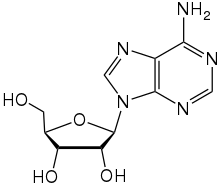

Psychoactive drugs are divided into different groups according to their pharmacological effects. Commonly used psychoactive drugs and groups are listed below:

- Hallucinogens, including psychedelics, dissociatives, and deliriants. This category encompasses all substances that produce distinct alterations in perception, sensation of space and time, and emotional states.[22]

- Examples: psilocybin, LSD, DMT (N,N-Dimethyltryptamine)/ayahuasca, mescaline, Salvia divinorum, Nitrous oxide, and Scopolamine

Certain psychoactives, particularly hallucinogens, have been used for religious purposes since prehistoric times. Native Americans have used peyote cacti containing mescaline for religious ceremonies for as long as 5700 years.[37] The muscimol-containing Amanita muscaria mushroom was used for ritual purposes throughout prehistoric Europe.[38]

The use of entheogens for religious purposes resurfaced in the West during the counterculture movements of the 1960s and 70s. Under the leadership of Timothy Leary, new spiritual and intention-based movements began to use LSD and other hallucinogens as tools to access deeper inner exploration. In the United States, the use of peyote for ritual purposes is protected only for members of the Native American Church, which is allowed to cultivate and distribute peyote. However, the genuine religious use of peyote, regardless of one's personal ancestry, is protected in Colorado, Arizona, New Mexico, Nevada, and Oregon.[39]